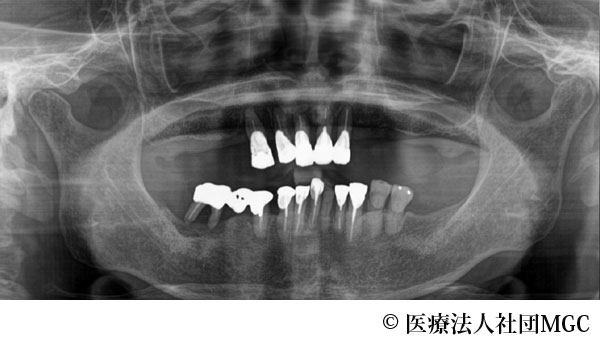

【症例3】上下All-on-4(オールオンフォー)

- 治療前

- 治療後

- 治療名

- 上下All-on-4(オールオンフォー)

- 費用

- 5,888,300円(税込)

- 期間

- 6ヵ月

上のブリッジが取れたことをきっかけに、全体に歯をきれいにしたいとご来院されました。

ご相談の結果、患者様の生活の質(QOL)を向上させ、しっかり噛め、審美的にも重視した、上下All-on-4(オールオンフォー)を行いました。

機能性、審美性ともに改善し、満足していただけました。